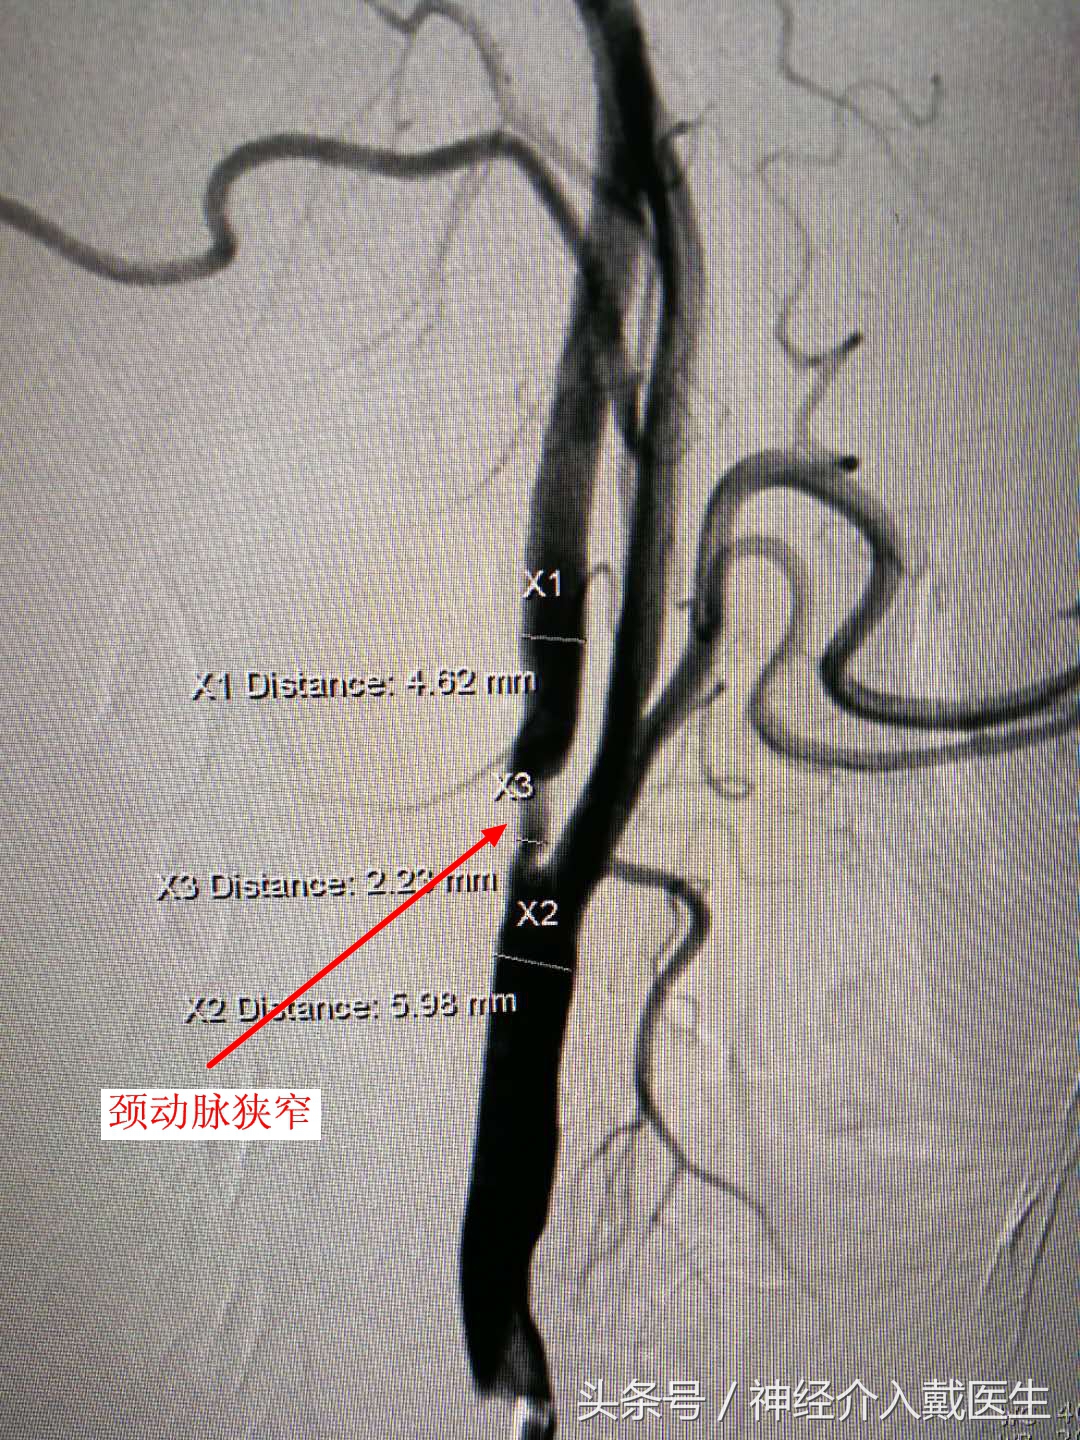

颈动脉狭窄分级:根据其狭窄率有四个不同程度的分级,狭窄率在50%以下的为轻度狭窄,狭窄率在50%-70%的为中度狭窄,狭窄率在70%以上的为重度狭窄,而如果狭窄率达到100%,那就是颈动脉闭塞了,这是非常危险的情况。